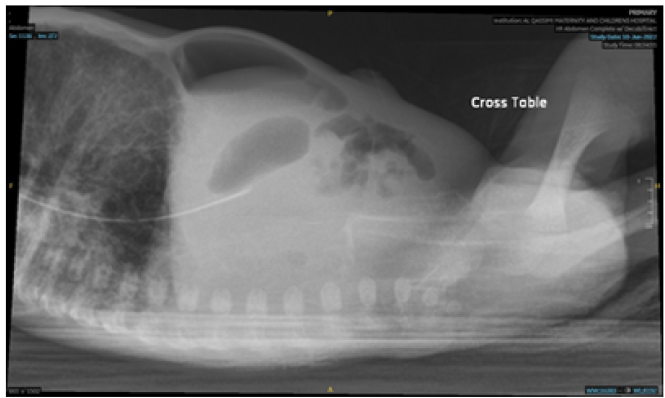

Pneumoperitoneum in an Extremely Preterm Neonate. Can it be an Innocent Finding? Case Report

Mohamed Abouseif Badawi, Mona Khalaf, Ahmad Dana and Anaam R Alhadeethi. 12(2): 19-24.